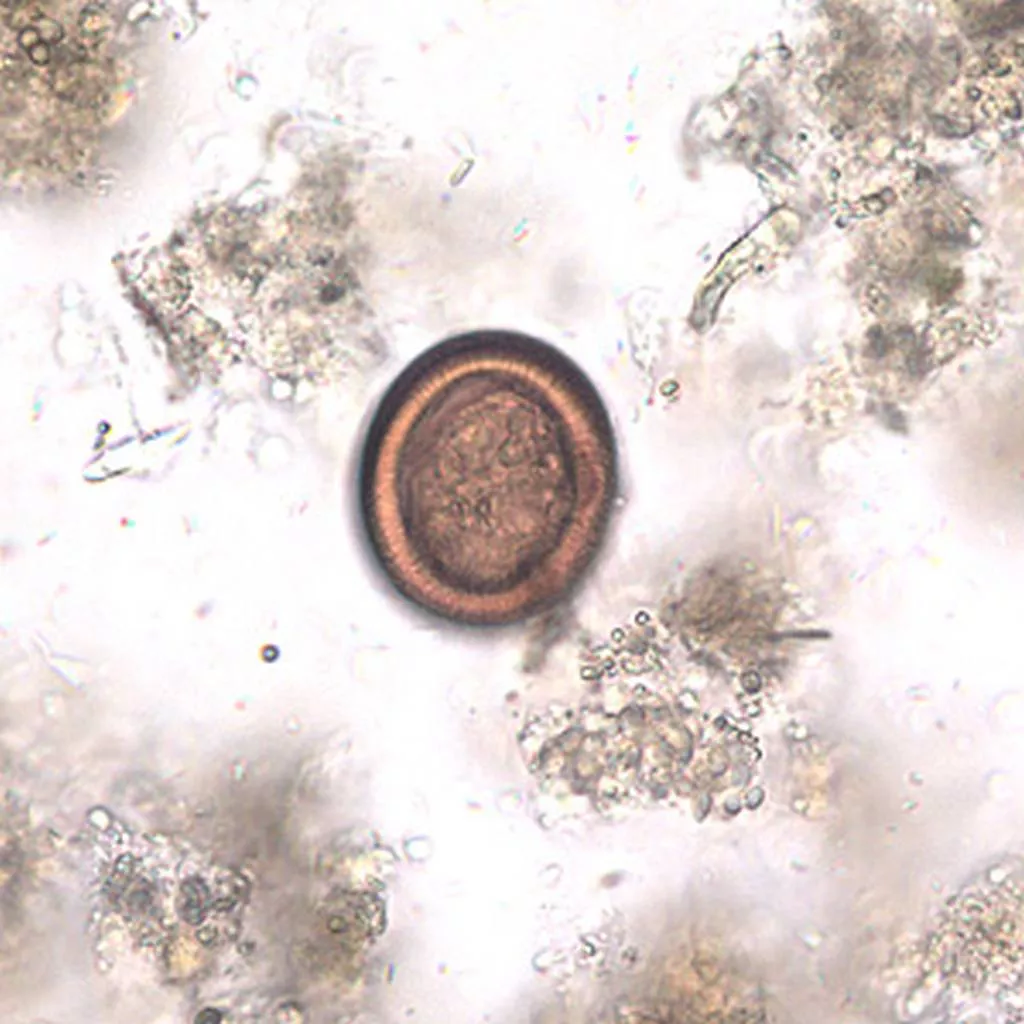

A kutyák székletével ürülő peték a tényleges köztigazdáknak számító növényevő állatokba kerülnek, melyek lárvákkal tűzdelt húsa nyilván nem egy egészséges étel (főleg ha nem sütik, főzik meg jól), de maga az ember többnyire a kutya székletével ürülő peték lenyelése miatt fertőződik.

A lenyelt peték – túlélvén a gyomorsavat és az emésztőenzimeket – a bélnyálkahártyába hatolnak, innen a vérárammal jutnak legkedveltebb helyükre, a májba. Csaknem egynegyedük a tüdőben köt ki, kis részük akár a vesékben, agyban, csontokban és más szervekben, szövetekben is képes megtelepedni (pl. nyelvben, szemben).